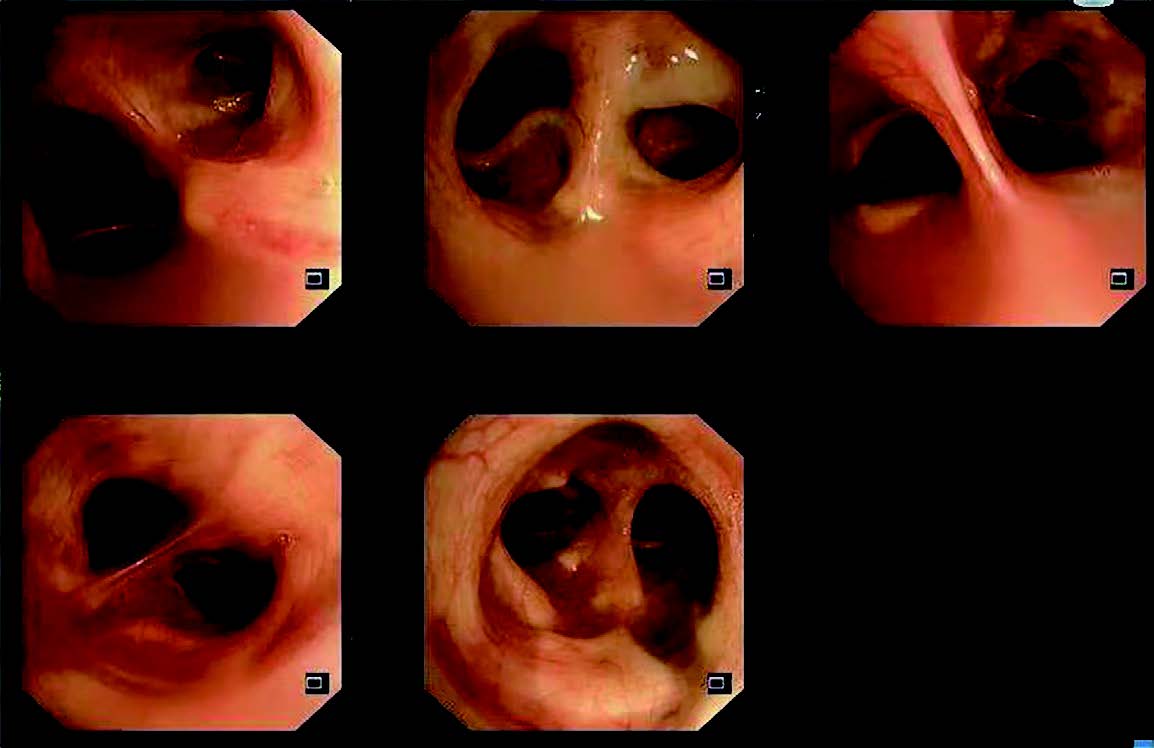

A 68-year-old female patient was admitted to respiratory department of our hospital for repeated cough and expectoration for 20 years, with her symptoms worsening for past 3 weeks. The patient had cough with white sticky sputum without hemoptysis, chest tightness, shortness of breath or fever. She visited outpatient department (OPD) of our hospital and underwent chest CT which showed bronchiectasis. After 2020, the symptoms recurred twice every year. The patient visited another hospital and was diagnosed as bronchiectasis with infection. After receiving intravenous antibiotics, her symptoms improved. One year ago, she began to cough up yellow purulent sputum with no fever. She went to the hospital again and took oral Levofloxacin intermittently, which improved her symptoms. On June 2022, the patient visited OPD of our hospital. Her chest CT showed scattered patchy opacities over bilateral lungs and bronchiectasis of middle lobe of right lung and lingual of left lung (Figure 1). She was given oral anti-inflammatory drugs for one week. However, after taking it, she still had expectoration and chest tightness, without fever or shortness of breath. So, she was admitted to our hospital for a treatment. Since the onset of the disease, the patient had a sound sleep, normal appetite, bowel and bladder habits and no significant weight loss.

Figure 1

Figure 1: Chest CT imaging. (A) Chest CT scan showed scattered patchy opacities over bilateral lungs and bronchiectasis of middle lobe of right lung and lingual of left lung. (B) Sagittal chest CT imaging.